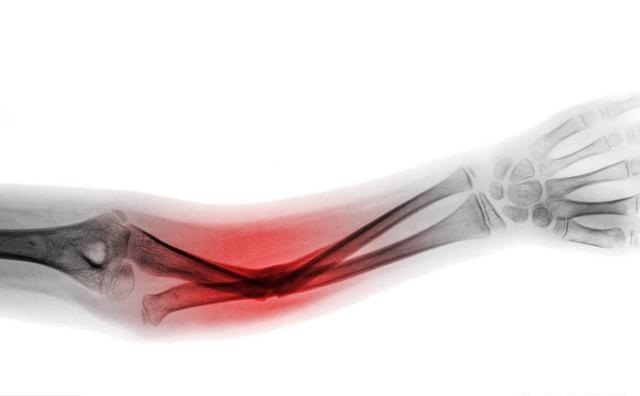

3、畸形

当肢体弯曲成你想象不到的角度的时候,可能瞎子都知道骨折了,这个毋庸置疑!甚至有一些骨折断段都已经戳破皮肤,露到外面来了,这个时候肯定骨折了!

1、X线检查

虽然不能一点小伤就去医院做检查,但是这个是判断是否有骨折的一个标准!并不是每一个骨折都是整个骨头断了,瞎子都能看出来的,有一些小型的骨折,只有在X光片下放大才能看得清楚。

检查也不贵,若想及时知道自己有没有骨折,及时做一个,在骨科医生阅片后即可诊断。有骨折早期处理,没骨折自己也放心一点。